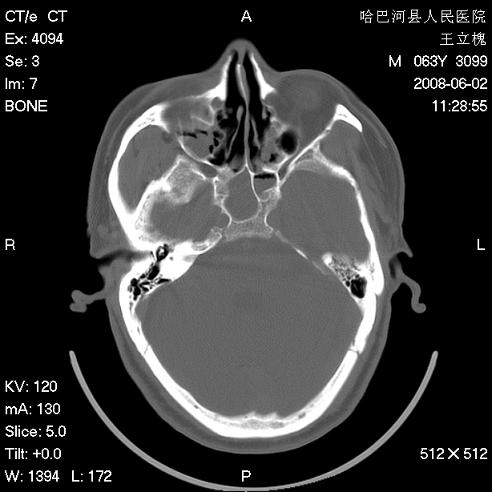

标题: CT13803:反复性鼻塞、流涕一年余 [打印本页]

标题: CT13803:反复性鼻塞、流涕一年余

副鼻窦炎,右上额窦积脓。左眼肌锥内见致密影,视神經受压

1.全组副鼻窦炎2.双侧上颌窦积液

1)全副鼻窦炎(左侧上颌窦黏膜下囊肿或息肉)。2)左眼眶肌锥内不规则小结节状软组织密度影;考虑为小血管瘤可能。建议行ct增强扫描检查。

全组副鼻窦炎,左侧肌锥内不规则形软组织肿块影,与眼外肌密度相当,左侧视神经受压,肿块与视神经及眼外肌分界清晰,眼外肌无增粗,眶壁无破坏,球后脂肪间隙不模糊,考虑良性改变,小血管瘤或神经源性肿瘤可能,建议增强扫描。

谢谢,增强扫描做了,眶内病灶与海绵窦同步明显强化,血管瘤